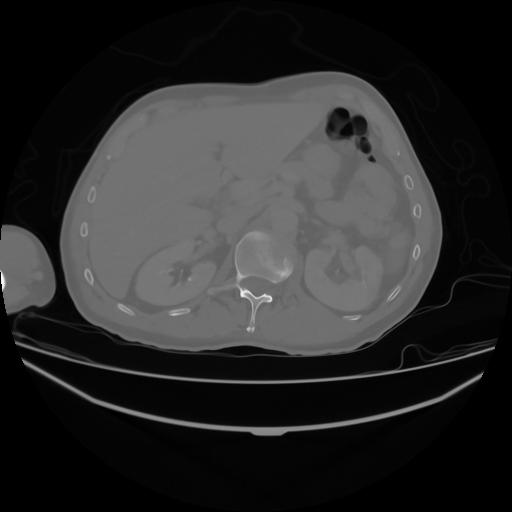

4 CUERPO,CE,Axial,3.0,CUERPO,,